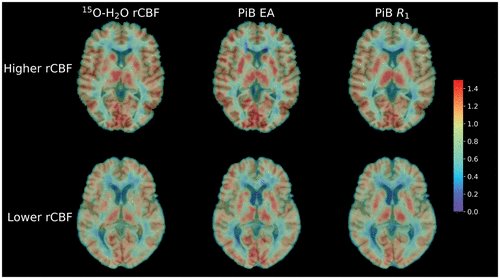

Surrogates of cerebral blood flow. http://ow.ly/ubcK50y5i7M

#hottopic#stroke#circulation#imagingpic.twitter.com/mogTDnuCoW